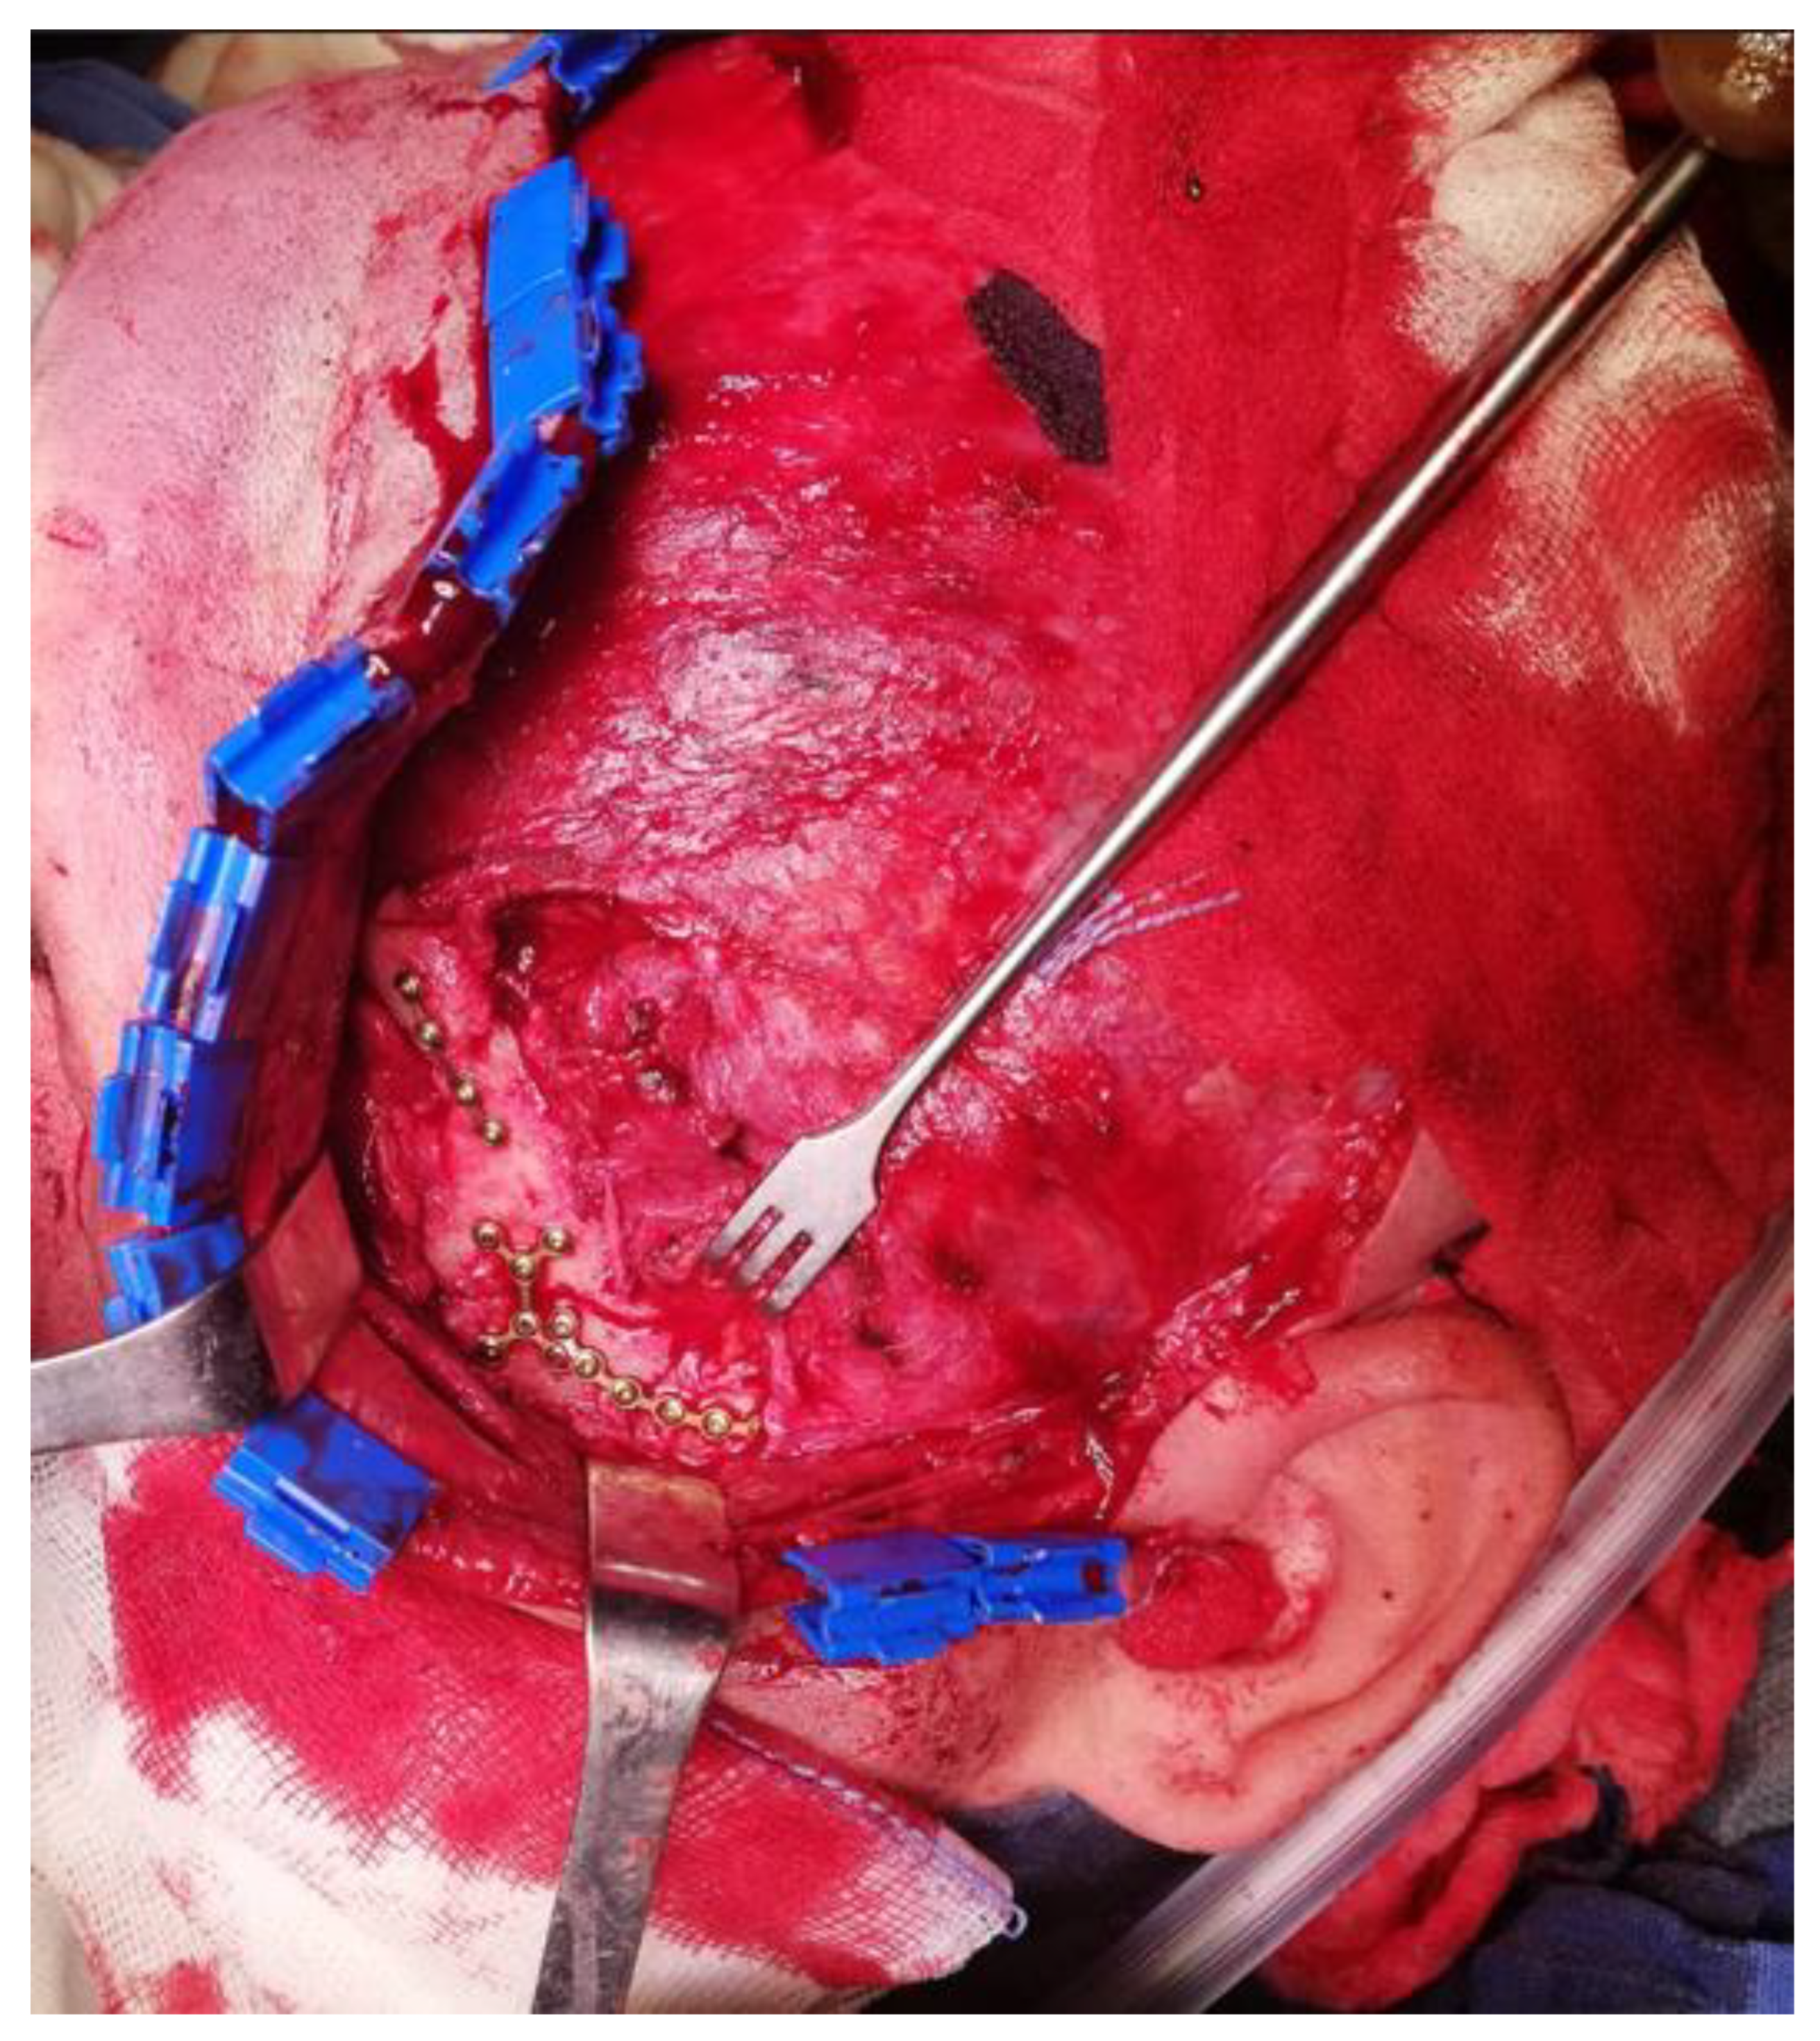

Figure 12. Intraoperative view after stable bone osteosynthesis via a hemicoronal approach.